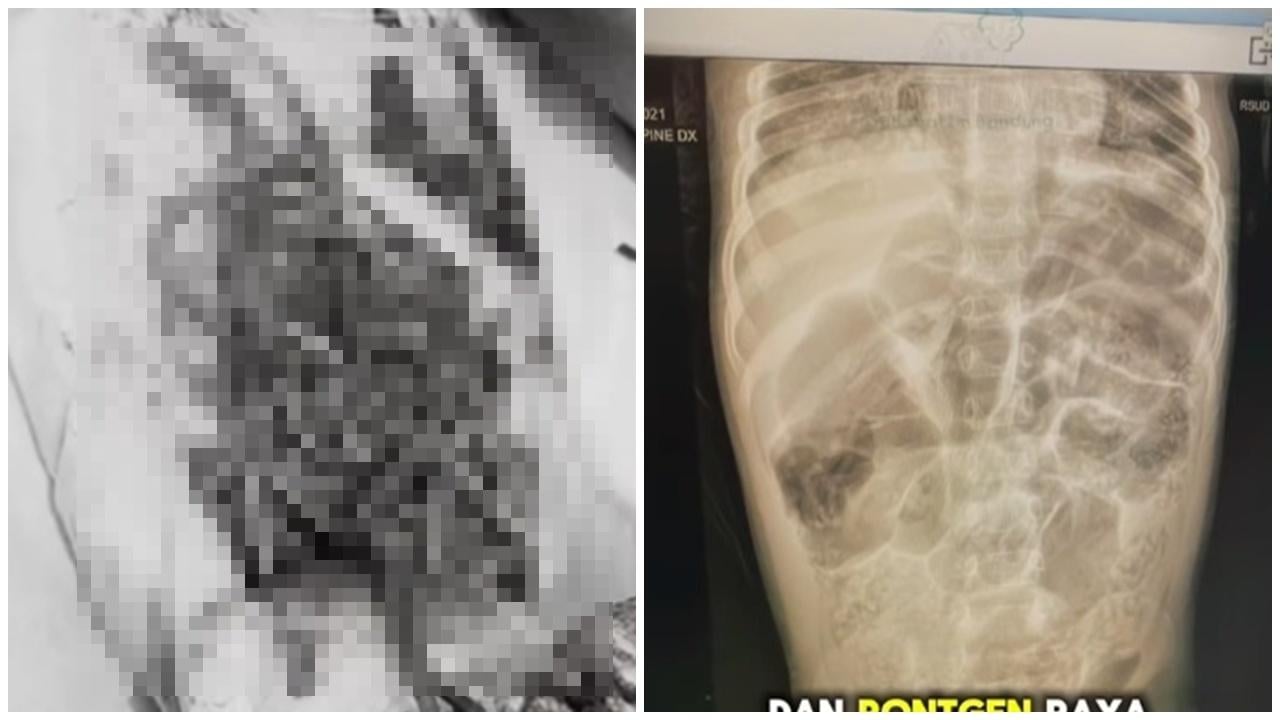

• 4歲女童鼻孔爬出15厘米活蟲,體內藏1公斤蛔蟲搶救10日亡。(IG)

4歲女童鼻孔爬出15厘米活蟲 體內藏1公斤蛔蟲搶救10日亡(慎入有片)

• 3歲男童腹脹便秘求醫,剖腹擠出3碗蛔蟲。(X)

3歲男童腹脹便秘求醫 剖腹擠出3碗蛔蟲